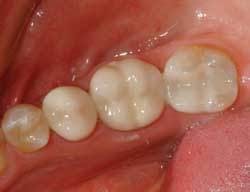

The time to begin the process of going metal-free has come upon the dental profession. The patients are asking to have their old restorations replaced with something more esthetic and biocompatible (Figures 1 and 2).

Quadrant dentistry is more rewarding to the dentist both monetarily and mentally. The new CAD/CAM technology provides an exceptional esthetic quadrant restoration, allowing for porcelain inlays, crowns, and bridges (Figure 4).

Patients no longer need to have the metal islands or metal second molars. The problem of “mismatching” the shades and esthetics of restorative materials seems to be solved.

Many different kinds of restorations can be done using the same porcelain. The entire quadrant can be restored with matching materials.